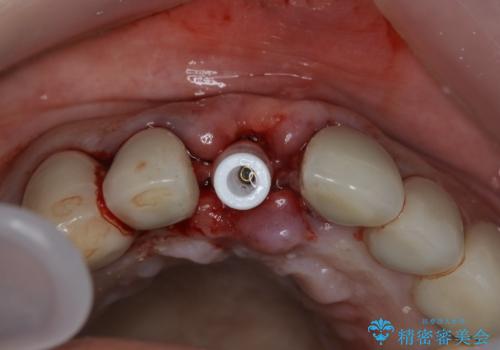

- 事故による外傷で前歯に歯根が真っ二つに折れてしまい、保存不可能となってしまった部分にインプラント治療を計画しました。

患者様のご要望もあり、審美性の確保ができる抜歯早期埋入→埋入後即時荷重という手術法を取りました。

近年、インプラントの素材や手術法の研究が進み、保存不可能となった歯牙に対して抜歯してすぐインプラントを埋入し、さらに直後から仮歯がを入れ噛むことができる【抜歯即時埋入】【即時荷重】という技法が確立されました。

それと比較すると、今回の方法では骨にしっかりと固定されているインプラントに単独で仮歯を装着することができるためフロスも通せますし、ある程度負荷のかかる食事も気にせずできるようになります。